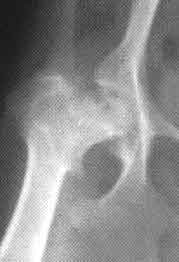

Radiographic (X ray) signs of Legg Perthes are usually gross and discouraging, since many cases are not referred to the vet or the specialist for diagnosis until the dog has been limping for a long time or the disease has progressed to the point that it becomes a more real problem to the owner. These small dogs put so little weight on their tiny hip joints that they almost can compensate for discomfort by “walking on their forelimbs instead of their four limbs.” Many are “couch potatoes” or spend much time being carried, but even then, picking up an affected dog in a certain manner can put more pressure on the joint than normal locomotion, so pain at that time is often the stimulus to do something about it. Owners and vets have reported “incredible pain” and constant, progressive discomfort, inability to stay long in any one position, and bone lysis (loss through a process akin to dissolving or consuming) at other areas in the limb distal (further away, the opposite of proximal) to the hip.

These are similar to those in LCPD. The earliest radiographic signs of LCPD, should you look for them before they change, include an increased radiodensity (opacity as seen on the radiograph) in the lateral part of the epiphysis of the femoral head. Lateral means the part away from the mid-line or medial; the “outside.” Resorption of necrotic (dying, rotting or decomposing) trabecular bone cells is next, accompanied by a lysis (dissolving or being consumed) of bone. These are replacement attempts by the body, similar to the attempt to replace bone that takes place during HD remodeling; eventually there is fracture or collapse, like a frame house riddled by termites. As HD may or may not be concurrent, the congruity of the ball and socket coxofemoral joint might still be maintained until collapse.

| Legg-Perthes is mostly found in Toy breeds. | Legg-Perthes; showing necrotic femoral head | Legg-Perthes necrosis with HD |